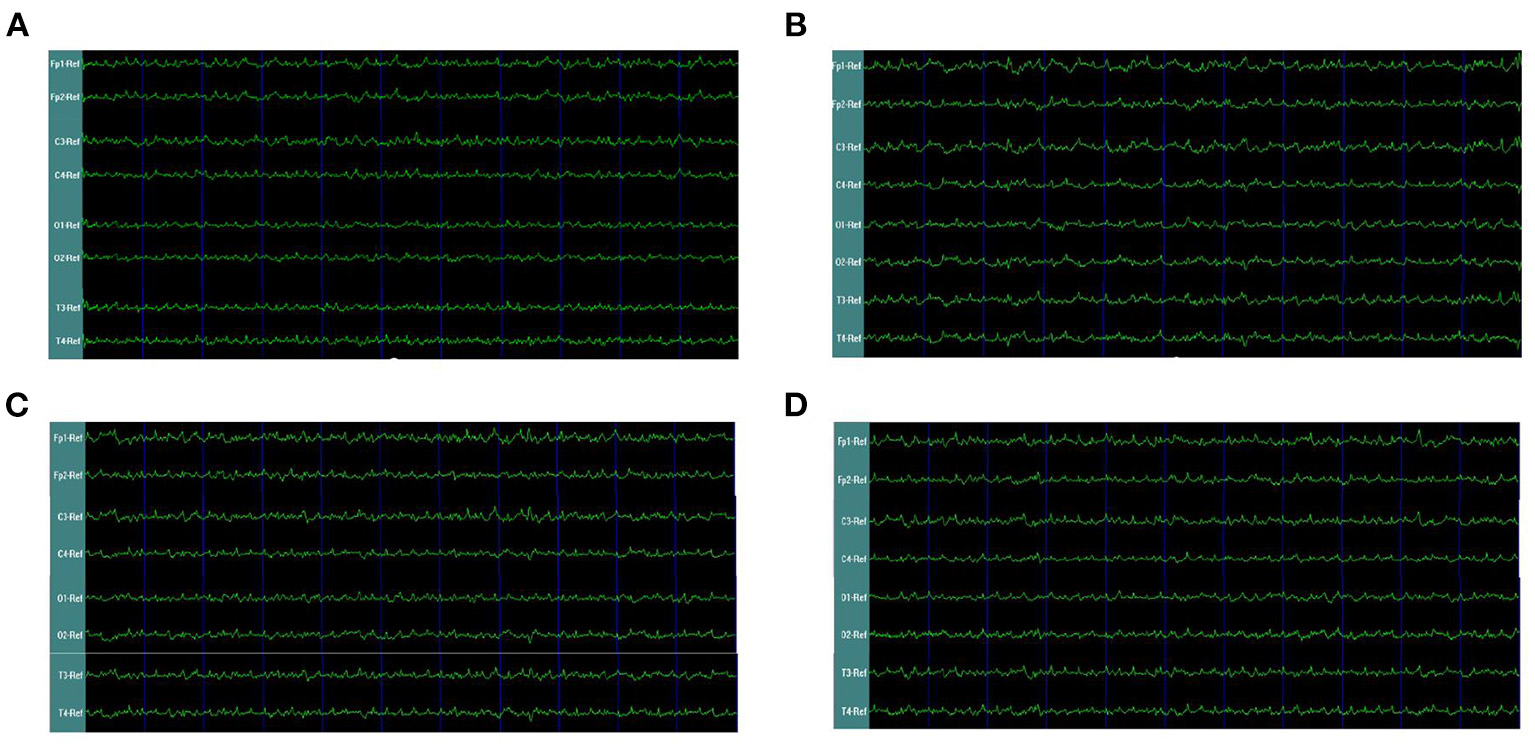

In the rats with moderate to severe TBI on the right side, the EEG pattern was shown in Figure 2. The gamma oscillation we recorded after TBI showed a significant decrease in cortex electrodes Fp2 (P = 0.002), T4 (P = 0.001), C4 (P= 0.009), and O2 (P = 0.001) (Figure 3A). After 1 week of 40 hz Blue LED intervention, the gamma oscillation of rats significantly increased in these cortex electrodes, Fp2 (P = 0.001), T4 (P < 0.001), C4 (P < 0.001), and O2 (P < 0.007), compared with the TBI (R,7d) group (Figure 3B, Table 2).

Figure 2

EEG waveforms of right-side TBI in rats. (A) EEG waveforms of control subgroup (B) EEG waveforms recorded immediately after TBI (C) EEG waveforms of 7 days after TBI without treatments (D) EEG waveforms of TBI after 7-days treatment of 40 hz Blue LED.